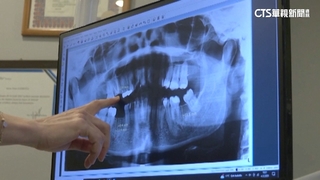

來到三民區一處旅館逮人,現場還查扣300多件的,醫療相關器具證物,而遭查獲的女移工,是個地下牙醫,移民署高雄專勤隊隊長趙志成說:「咪女疑似上網看影片自學矯正技術,且不定時在網路公布,預約醫美療程時段與地點。」

合法來台工作已經8年,一年多前開始上網自學整牙技術,接著拍了抖音影片宣傳,以比市價還要便宜約10分之一的價格,吸引同鄉進行整牙療程,來到女移工被逮的飯店,櫃檯人員說,假日來找女移工的人不少,飯店櫃檯人員VS.記者說:「就禮拜六比較多吧(禮拜六喔禮拜天沒有),她們就住到禮拜天啊。」

只是邊做邊學,也因此做出不少問題,而遭到同鄉檢舉,目前全案已依違反醫師法,非法執行醫療業務罪等規定,移請高雄地檢署偵辦,也提醒民眾,進行牙齒相關療程,一定要找合格牙醫,不要貪便宜找上密醫,整壞牙齒可是賠了夫人又折兵。